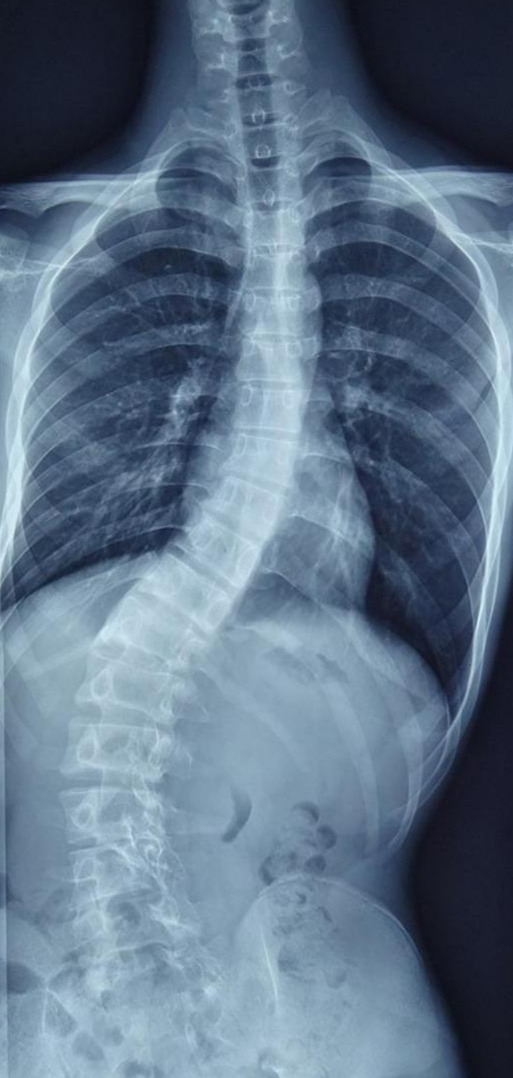

首先让我们看一例青少年脊柱侧弯

这是一名13岁患者,从小脊柱就有些“歪”,但是家长一直未予以重视。随着孩子逐渐进入青春期,身体逐渐长高,脊柱却“歪”的越来越厉害,而且出现了二便*禁失**,从影像学我们发现,他不仅存在脊柱侧弯,还存在许多其他问题。

患者腰骶部存在一个团状异常信号,有可能是脂肪瘤甚至畸胎瘤,同时合并硬脊膜膨出。此外MRI显示患者的脊髓并没有随着生长发育向上移动,而是与远端“有所牵挂”,腰部的神经像一根根弓弦与远端相连,也就是医学上所称的“脊髓栓系”。患者二便*禁失**很可能就是由于身体逐渐长高,产生脊髓栓系后导致的。

手术不仅要解决侧弯,还要减压神经,解除栓系,改善神经功能。